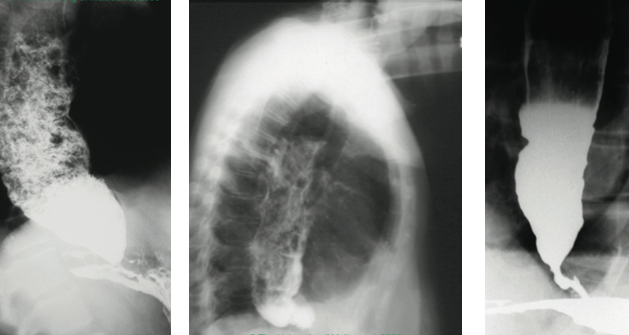

Achalasia

Oesophageal cancer (SCC)

Oesophageal cancer (adenocarcinoma)